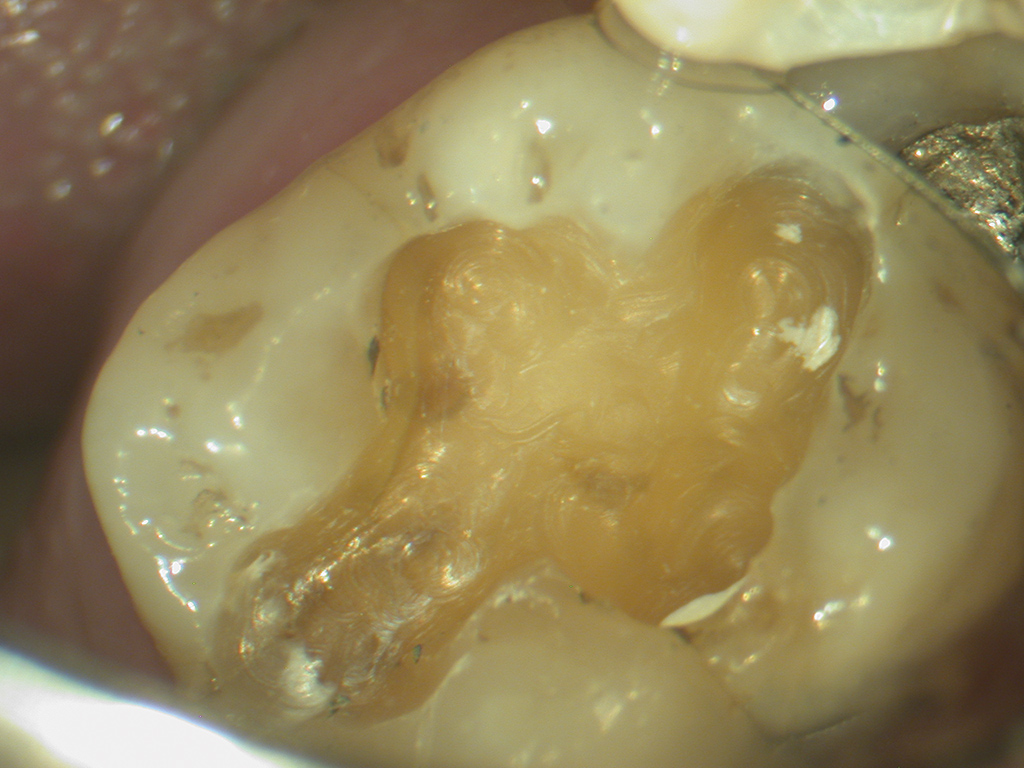

The modern philosophy is completely opposite to what it was at the turn of the 20th century. Conservation of tooth tissue is now the most important factor and this has been made possible due to the large increase in the number of materials which are now available. The disease should be manage, i.e. the caries removed, the cavity examined and THEN the appropriate material selected (Fig 1).

- Figure 1 – Once the caries has been managed then the most appropriate material to restore the cavity should be chosen